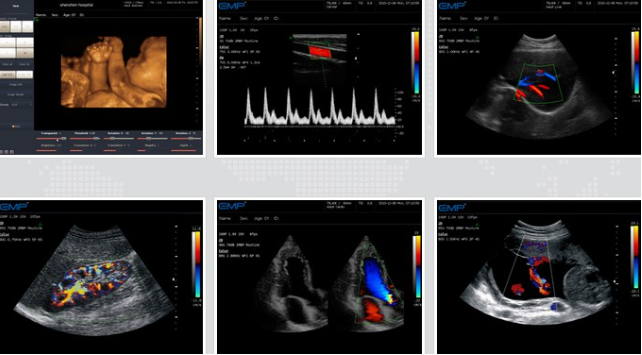

超声影像图

方案介绍

无创、无辐射:超声影像图检查不会对人体造成任何损伤,适用于各个年龄段和孕妇等特殊人群。

操作简便、成本低廉:超声检查操作相对简单,成本较低,可以在临床实践中广泛应用。

高分辨率:超声对人体软组织有良好的分辨能力,有利于识别生物组织的微小病变。

实时性:超声检查常常能提供实时的图像信息,使医生能够快速准确地进行诊断。